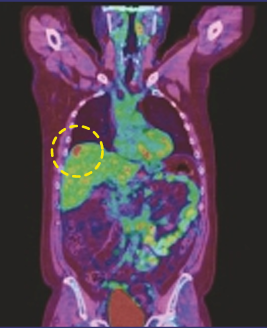

CASE [PET-CT Fusion]

15 min (50%) Scan Without Denoising

15 min (50%) Scan With Denoising

30 min (100%) Scan Standard